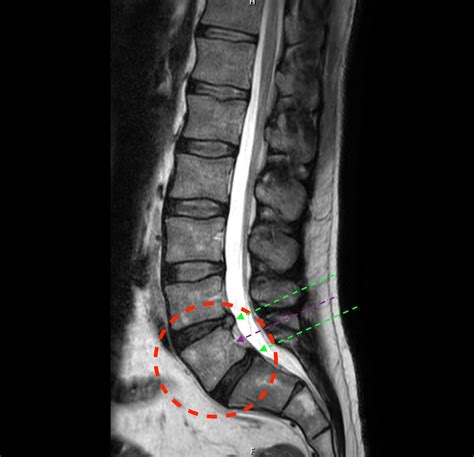

Accurate diagnosis of conditions affecting the lumbosacral transitional segment is essential for effective treatment. Several diagnostic methods are commonly used to evaluate this region:

• Imaging Studies: Imaging techniques such as X-rays, MRI, and CT scans are crucial for visualizing the anatomy of the lumbosacral region. These studies can reveal degenerative changes, herniated discs, spinal stenosis, and other abnormalities.

Advances in technology have significantly improved the diagnosis and treatment of conditions affecting the lumbosacral transitional segment. Imaging techniques, such as MRI and CT scans, provide detailed visualizations of the spine, allowing for accurate diagnosis and treatment planning. Surgical techniques, such as minimally invasive procedures, offer less invasive options for addressing structural issues in the spine.

Imaging techniques, such as MRI and CT scans, provide detailed visualizations of the spine, allowing for accurate diagnosis and treatment planning. These techniques can reveal degenerative changes, herniated discs, spinal stenosis, and other abnormalities. Surgical techniques, such as minimally invasive procedures, offer less invasive options for addressing structural issues in the spine. These procedures can reduce recovery time, minimize scarring, and improve outcomes.